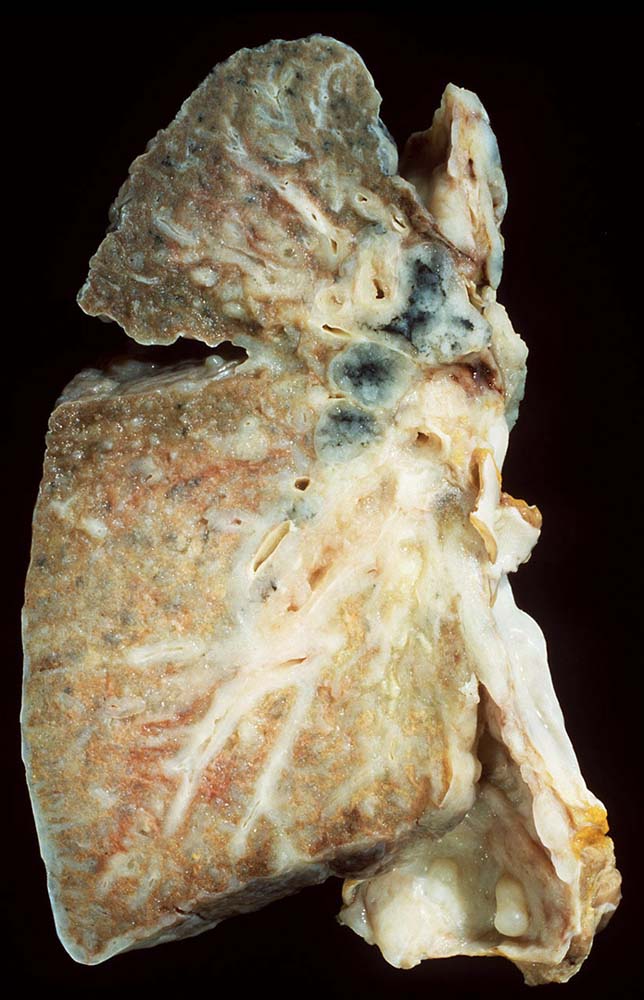

Das metastatische Wachstumsmuster von primären Bronchuskarzinomen und extrapulmonalen Tumoren innerhalb der Lunge ist variabel. Hämatogene Metastasen imponieren makroskopisch als multiple scharf begrenzte rundliche Knoten in allen Lappen meist in peripherer Lage. Der metastatische Befall von Lymphknoten kann durch direkte Tumorinfiltration durch den Primärtumor erfolgen (=per continuitatem) oder über die Lymphgefässe. Bei einer ausgeprägten lymphogenen Tumorausbreitung erscheinen subpleurale mit Tumor gefüllte Lymphgefässe makroskopisch als prominente weisse Streifen. Mikroskopisch lassen sich Tumorinfiltrate in peribronchialen und perivaskulären Lymphgefässen nachweisen (=Lymphangiosis carcinomatosa). Hepatozelluläre Karzinome metastasieren typischerweise in Form von Tumorembolien (> 1279) hämatogen in die Lunge.

• Sternförmiges Karzinom mit zentraler Vernarbung mit reichlich schwarzem Anthrakosepigment.

• Peritumorales Lungenemphysem (Traktionsemphysem).